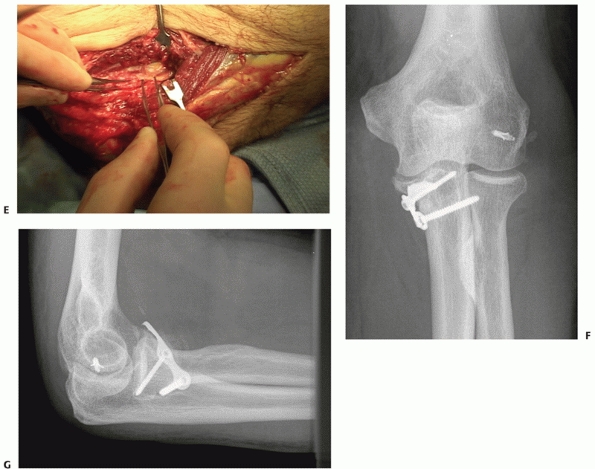

![]() |

FIGURE 32-19

Anterior (or trans olecranon) olecranon fracture-dislocations are relatively uncommon injuries that are characterized by anterior translation of the forearm, an intact radial head, and fracture of the proximal ulna. A. This very complex proximal ulna fracture involves the coronoid process. B. The coronoid is split in the sagittal plane and can be repaired with interfragmentary compression screws. C. The metaphyseal and diaphyseal fragmentation is bridged with a long plate, contoured to wrap around the dorsal surface of the ulna. Tension wires are used to enhance fixation of the small proximal fragments. D. Six months later, the fracture is healed and good elbow function has been restored. |

|

FIGURE 32-20 Posterior olecranon fracture-dislocations can be very complex injuries. A. In this patient, the coronoid and radial head are fractured. B. The coronoid is split into three fragments. (continues)

FIGURE 32-20 (Continued) C. A posterior skin incision discloses muscle injury. D.

If the muscle injury is opened up and extended somewhat, the olecranon fragment can be translated proximally like an olecranon osteotomy, exposing the elbow articulation. E. An additional medial exposure with transposition of the ulnar nerve helps with manipulation of the anteromedial fracture fragment. F. The coronoid is split into three large fragments: anteromedial, central, and lesser sigmoid notch. G. A long dorsal plate is applied, bridging the comminution and securing the coronoid. H. The radial head is replaced. I. The anteromedial portion of the coronoid is secured with screws. Healing occured and good elbow function was restored. |